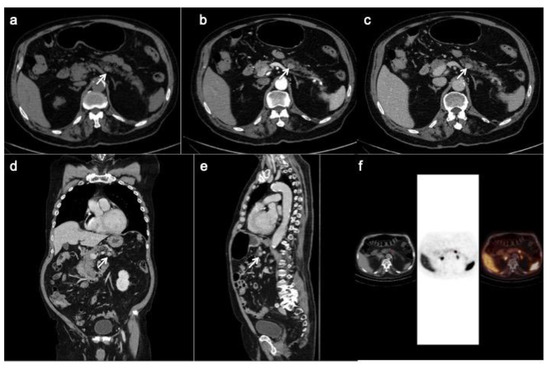

PET/CT with 68-Gallio labeled SSA is the imaging method of choice for panNEN functional study. There are mainly three available SSAs showing no substantial differences in patients staging: 68-Ga-DOTANOC, 68-Ga-DOTATOC (Figure 5) and 68-Ga-DOTATATE. All of them are SSRT2 high-affinity tracers; only 68-Ga-DOTANOC proved to have an affinity for SSRT3.

Figure 5.

CT images (a–c) show a hyper-enhancing pancreatic nodule in the body/tail of the organ (arrows) well depicted on the coronal (d) and sagittal (e) reconstruction too. The 68-Ga-DOTATOC PET/CT (f) shows focal uptake in the pancreatic lesion.

Compared to SRS, PET/CT has shown higher sensitivity and specificity for identifying receptor-positive panNENs [66]. Several studies on the diagnostic accuracy of 68-GaSSTA PET in gepNENs have demonstrated a sensitivity range of 88–93%, and specificity range of 88–95% [21]. PET/CT and CT should be considered as complimentary procedures for patients with a suspected panNEN. Indeed, Versari et al. calculated a CT sensitivity of 91% and a mean 92% with 68-Ga DOTA-TOC for detection of duodeno-pancreatic neoplasia [67].

Furthermore, this nuclear technique has other advantages: the study has a lower radiation dose for the patient, thanks to the 2 h protocol, in comparison to 24 h of SRS; 68-GA SSA tracers have a favorable normal biodistribution, with a lower liver up-take, which can increase metastasis detection rate; background physiological uptake is similar to Octreoscan, with prominent uptake in adrenal glands and in the uncinated process of the pancreas, so that can be misdiagnosed as panNEN [68]. Standardized uptake values (SUVs) are calculated for quantitative analysis, allowing a direct comparison among exams performed with the same radiotracer.